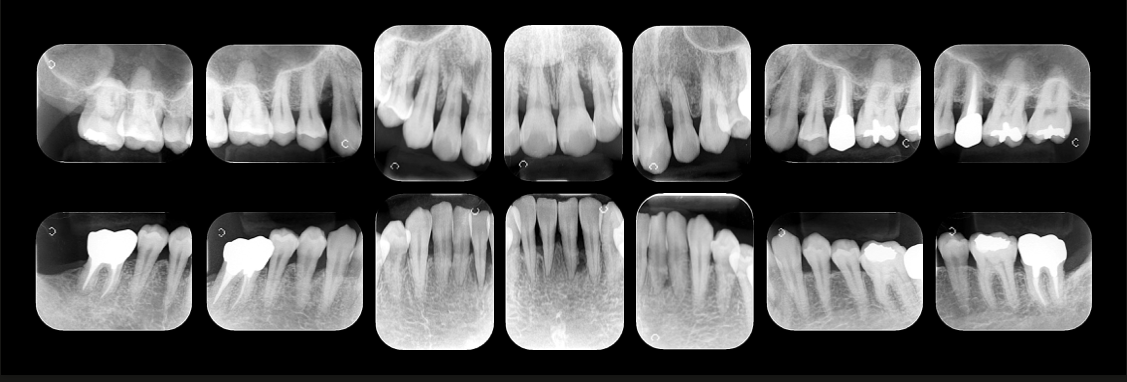

精密な診査診断

重度の歯周病で適切な治療計画を立案するためには、お口の状態を詳細に把握する必要があります。そのために当院では精密な診査診断を行います。歯周病の直接的な原因だけでなく、咬み合わせなどの間接的な原因も把握することによって、治療計画の精度が高まります。

歯周組織再生療法

通常抜歯の対象となる歯であっても、歯周組織再生療法を行うことで残せる可能性はあります。もちろん、適応条件はありますが上記の精密な診査診断を行うことで、歯を残せるか否かを判断することが可能です。重度歯周病だから”必ず抜歯”ということはありません。